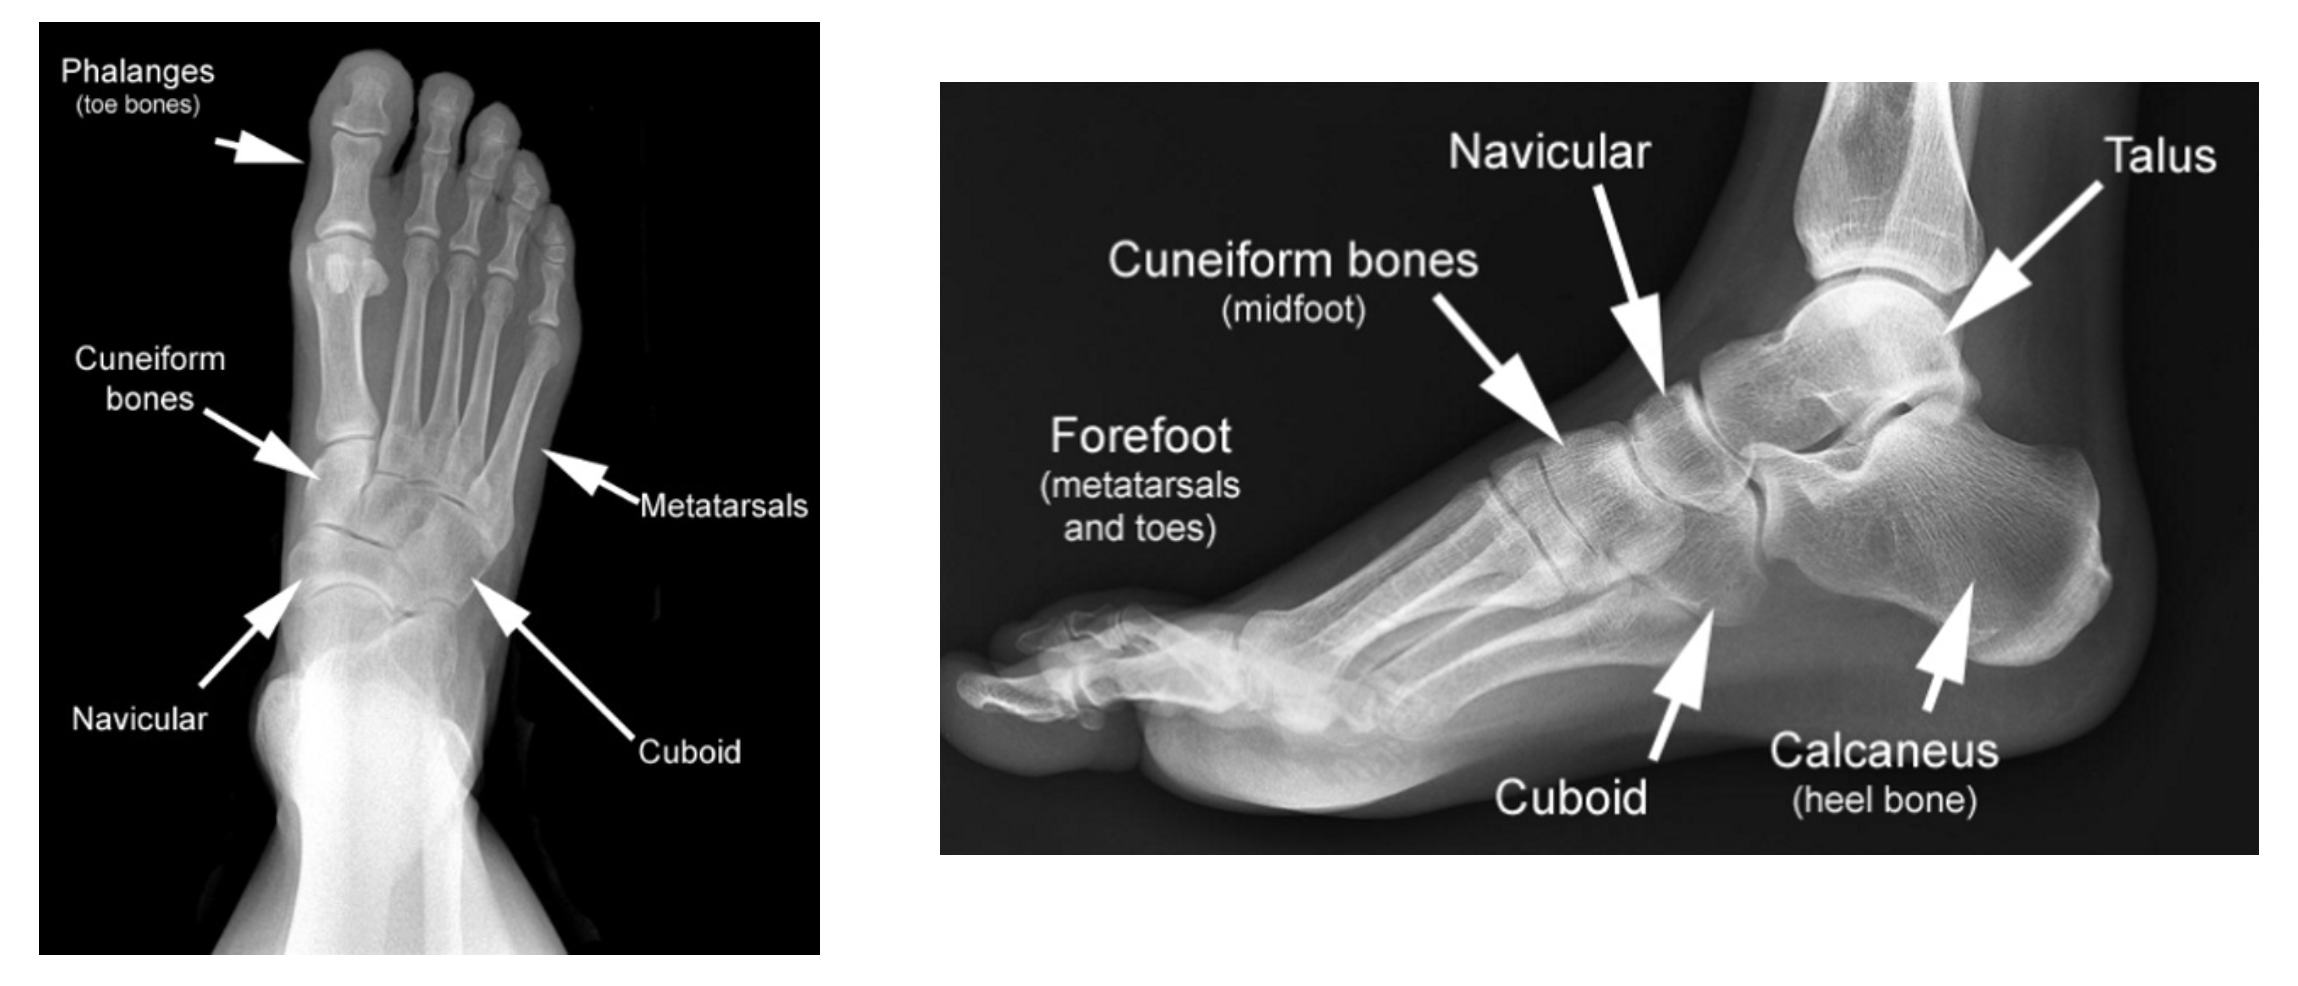

Based on “The feet and its toes (AY36)” by Moshe Feldenkrais

Follow Moshe Feldenkrais’ approach to softening and strengthening the feet, and feel the relaxation echo through your whole self. This lesson is written for lying and sitting on the floor. If you prefer to sit the whole time, you might want to set up near something to support your leg on.